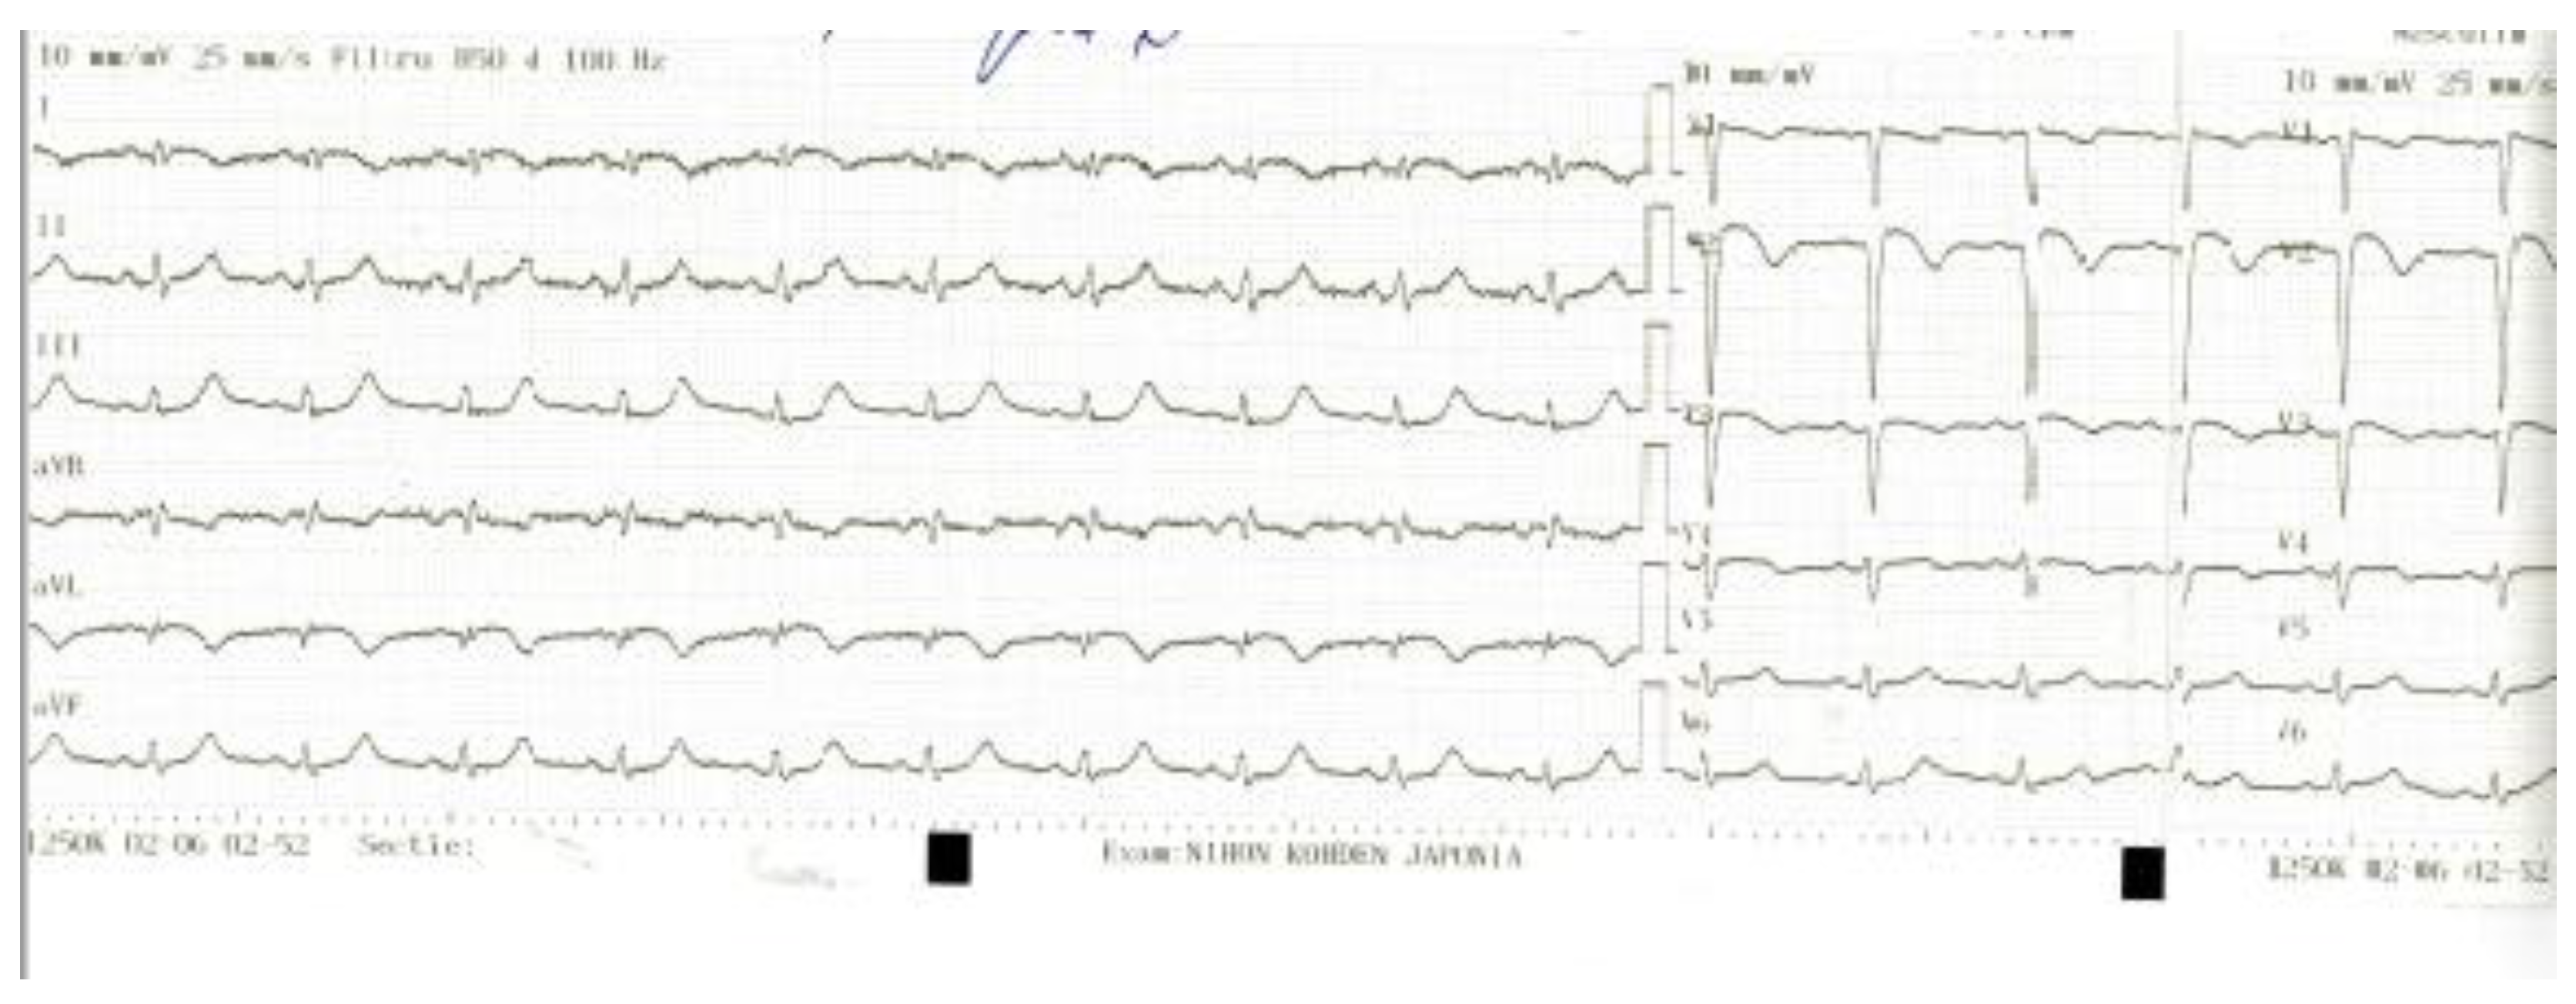

T and Small Protrusion (TAP) Technique in Bifurcations: Coronary Artery Disease in Acute Myocardial Infarction Patients after COVID-19 Pneumonia

2. Case Presentation